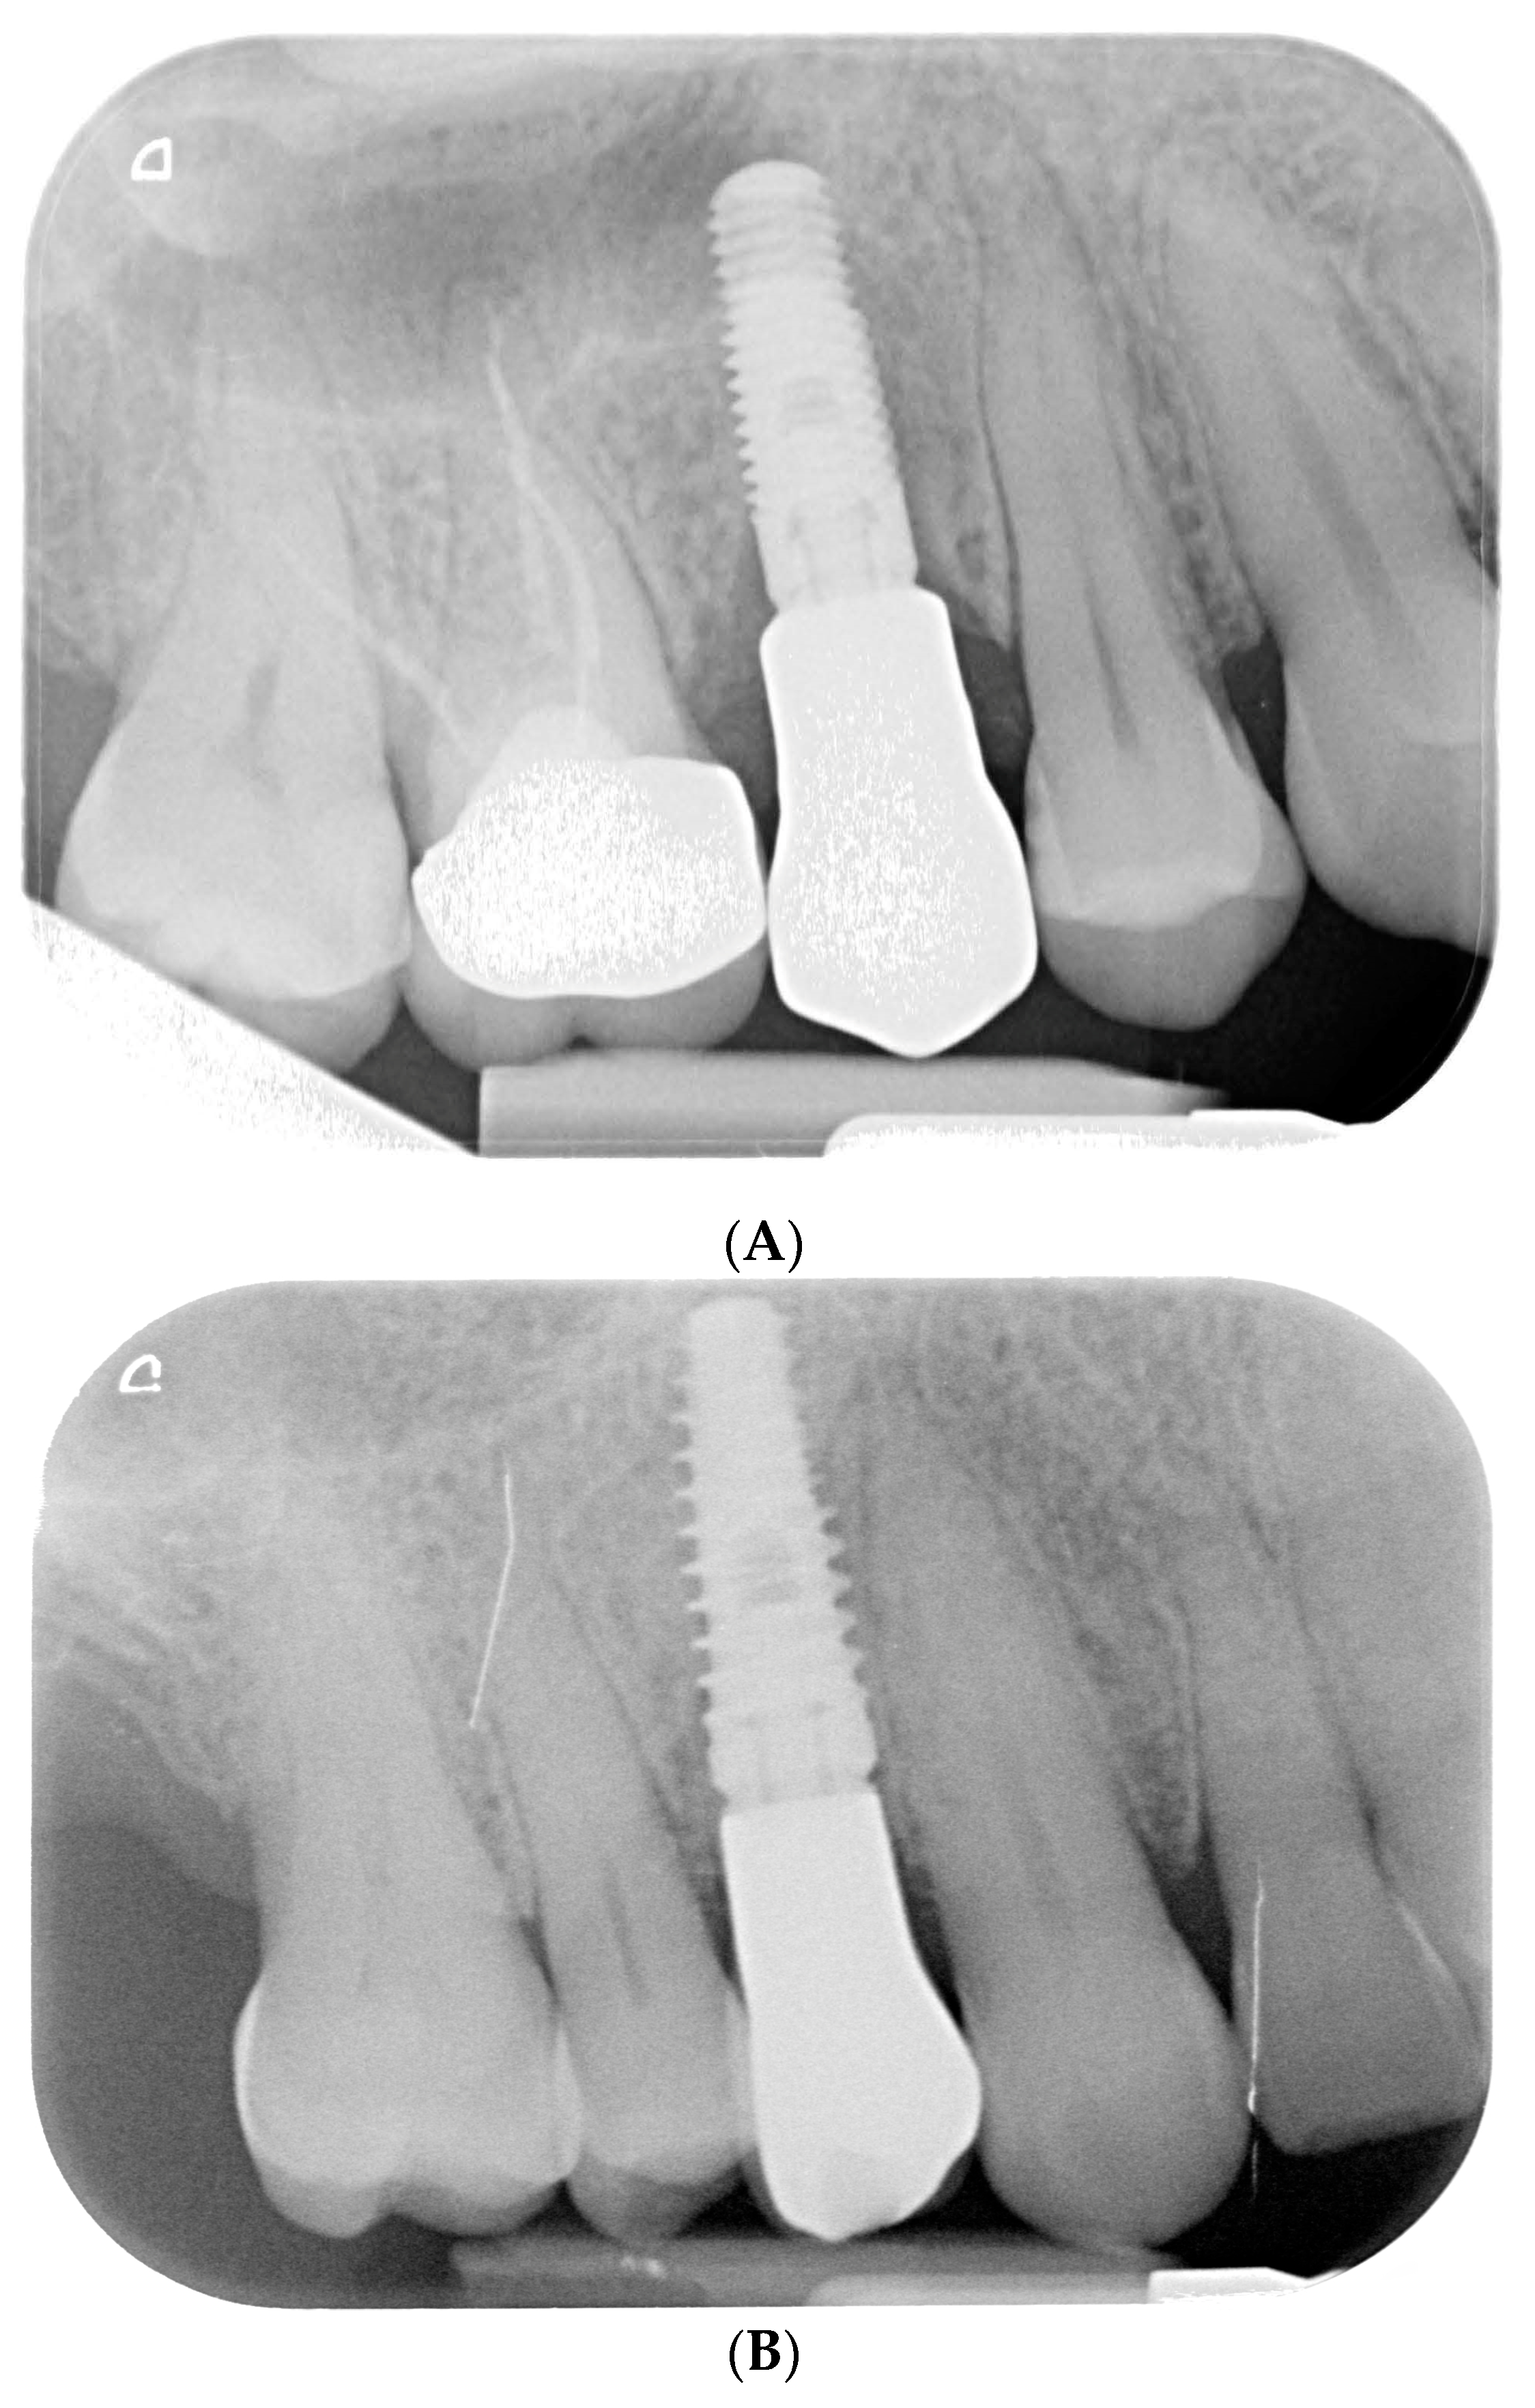

Figure 3.

Endoral RX prior to implant insertion: test group (A) vs. control group (B).

Preoperative examination addressed smile line, inter-arch relationship, and bucco-lingual bone thickness. Periapical radiographs and cone beam computed tomography (CBCT) were obtained to assess root dimensions, bone availability, adjacent structures, and implant planning. Preoperative periapical radiographs were taken using the VistaScan Mini Plus device (Figure 3) (Dürr Dental SE, Bietigheim-Bissingen, Germany).